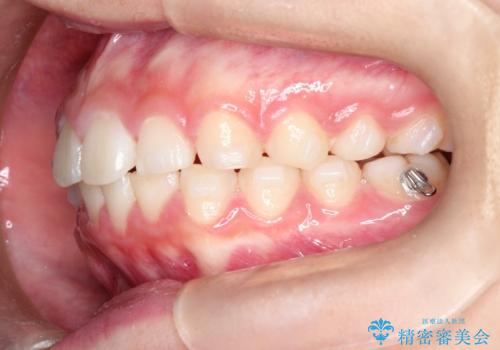

【インビザライン】出っ歯を引っ込めたい。

- 前歯の隙間と、出っ歯に見えることを主訴に来院されました。

できるだけ目立たない装置をご希望されましたので、インビザラインにて治療を行いました。

治療中は、できるだけ前歯を下げることができるように”顎間ゴム”を使用します。

”顎間ゴム”を利用することで、奥歯を後ろに動かす力を強めることができます。